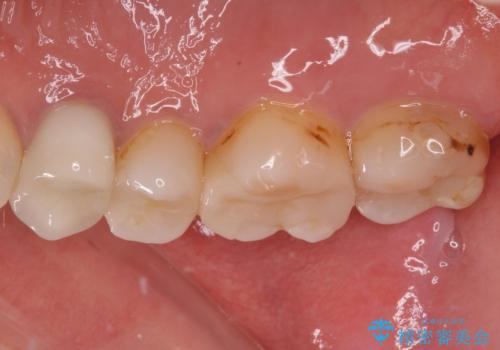

- 奥歯の詰め物や周辺の歯が欠けてしまったとのことで来院された患者様です。

上顎は、元々の詰め物が小さく、欠けた範囲も大きくなかったため、セラミックインレーにて修復治療を行うこととしました。

一方下顎は、元々のむし歯の範囲が広かったため、長期的な予後を踏まえ、セラミッククラウンにて補綴治療を行うこととしました。